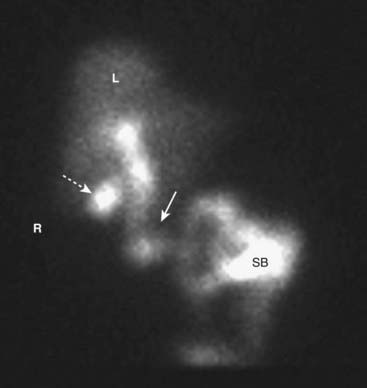

image In a normal HIDA scan, the bile ducts contain radiotracer within 10 minutes and there is radiotracer in the duodenum by 60 minutes, indicating patency of the common bile duct. Filling of the normal gallbladder occurs within 30 to 60 minutes, which confirms the patency of the cystic duct. Delayed images in several hours are usually obtained to reduce false positive results (Fig. 22).

image

Figure 22 Normal HIDA scan.

In a normal HIDA scan, the bile ducts (solid white arrow) contain radiotracer within 10 minutes, and there is radiotracer in the duodenum and small bowel (SB) by 60 minutes, indicating patency of the common bile duct. Filling of the normal gallbladder (dotted white arrow) occurs within 30 to 60 minutes, which confirms the patency of the cystic duct. Delayed images in several hours may be obtained to reduce false positive results. (R, Patient’s right side; L, liver.)

image Except in rare exceptions, visualization of the gallbladder excludes acute calculous cholecystitis.